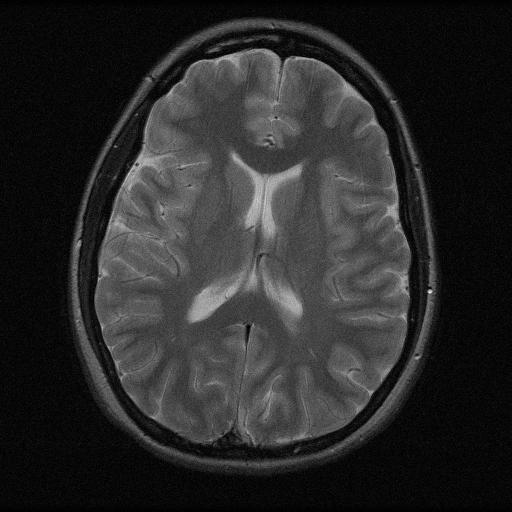

We illustrate our findings with numerical experiments, first consider various artificial setups in which we show that splitting a signal via local projections allows for accurate, stable, and robust estimation. We verify that by increasing the size of the fusion frame, a certain robustness to noise is also achieved. While the computational complexity remains relatively low, we achieve stronger recovery performance compared to usual single-device compressed sensing systems. We finally show how our techniques can be applied in various signal processing tasks such as Doppler signal denoising, natural scene scanning and reconstruction, and MR Image reconstruction. In these examples, we empirically verify that visually good reconstruction are obtained, even in highly undersampled and noisy regimes.

• [39] T. Zhang. Sparse recovery with orthogonal matching pursuit under rip. Information Theory, IEEE Transactions on, 57(9):6215–6221, 2011.